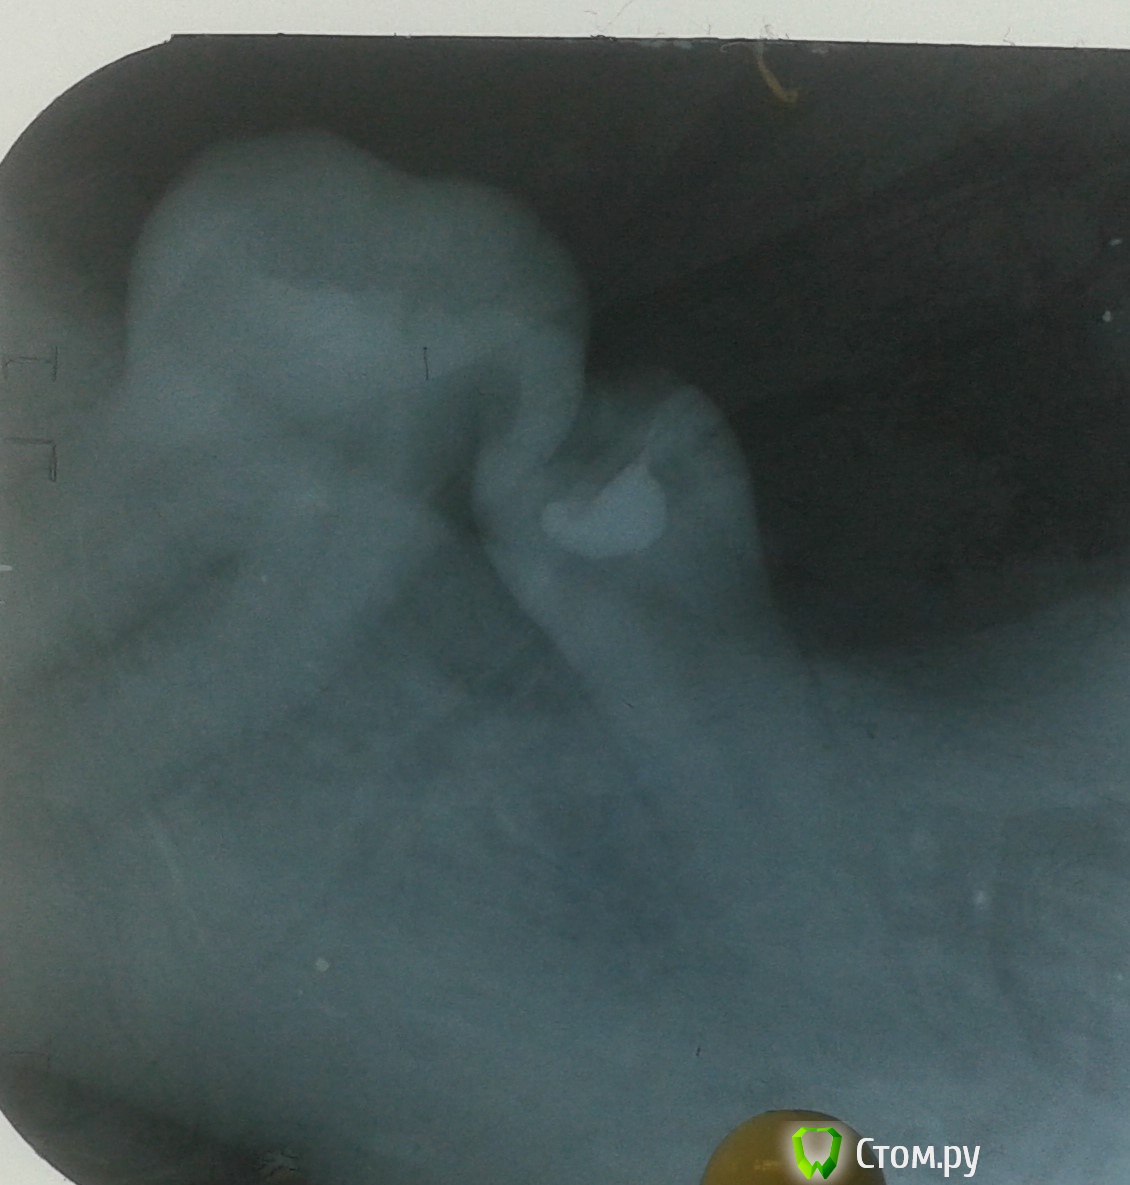

Molo4niy Опубликовано 21 октября, 2014 Поделиться Опубликовано 21 октября, 2014 Пациент,женщина 27 лет.Зубы в таком положении не менее 2-х лет(со слов пациента).Болевые ощущения появились 2 недели назад,перкусия положительная.Подскажите пожалуйста,как лучше поступить.(пациент бюджетный,скорой помощи снять боль и до свидание(((Спасибо. Ссылка на комментарий

Дмитрий Никитюк Опубликовано 22 октября, 2014 Поделиться Опубликовано 22 октября, 2014 Пациент,женщина 27 лет.Зубы в таком положении не менее 2-х лет(со слов пациента).Болевые ощущения появились 2 недели назад,перкусия положительная.Подскажите пожалуйста,как лучше поступить.(пациент бюджетный,скорой помощи снять боль и до свидание(((Спасибо.На вопрос, какие Вам женщины больше нравятся, блондинки или брюнетки, настоящий мужчина ответит - да!На вопрос кем жертвовать в Вашем случае, ответ может быть только один - никем. Сделайте эндо, устранив боль и раздвиньте зубы с помощью ортодонтических сепараторов. Это будет очень бюджетное решение, но в то же время Вы сможете соблюсти главный принцып медицины. 3 Ссылка на комментарий